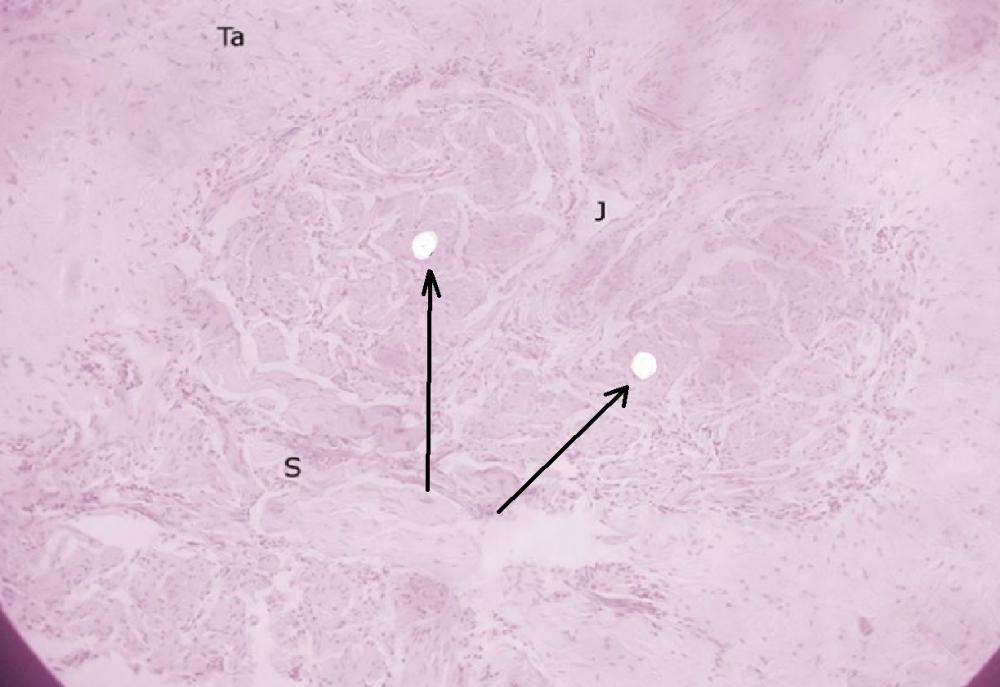

Pytanie 689

węzeł zespólniowy (łożysko, płyta kosmówkowa)